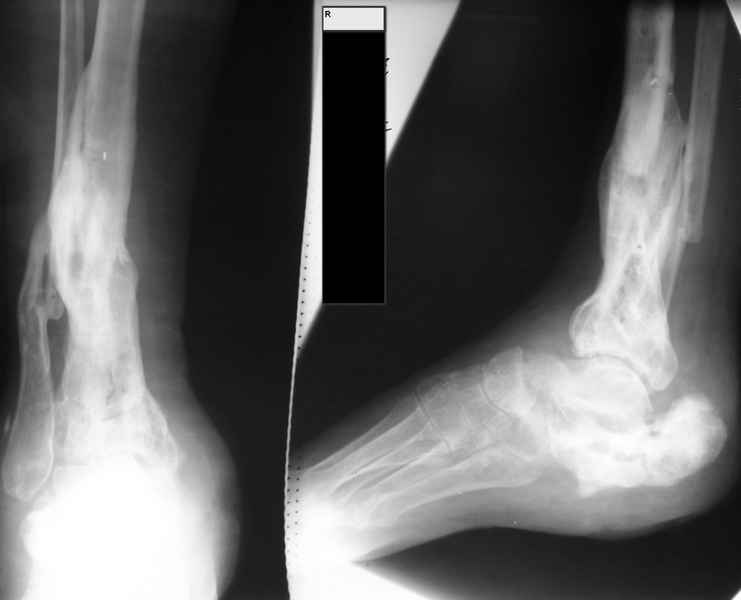

Молодая девушка со сросшимися многооскольчатыми переломами пяток и голеней.Young girl with fractures of the calcaneus Больная Н., 25 лет, падение с высоты (2008 г.). Жалобы на боли в области голеностопных суставах, в области пяток при ходьбе. Лечилась в аппаратах внешней фиксации по поводу открытых оскольчатых переломов обеих голеней, переломов пяток. Далее по поводу несросшихся переломов голеней –ЧКОС аппаратами внешней фиксации. Переломы срослись, аппараты демонтированы весной 2010г. В левой пяточной области в месте проведения спицы имеется сукровичное отделяемое. При ревизии гноя нет. Чем помочь девушке?

Patient N., age 25, falls from heights (2008). Complaints of pain in the ankles, in the heel when walking. She was treated by external fixation on open comminuted fractures of both legs, fractures of the calcaneus. Then she was treated by external fixation from nonunion of both legs. Now fractures are fused, apparatuses removed in the spring of 2010. How to help a girl?